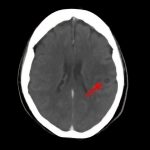

断層撮影